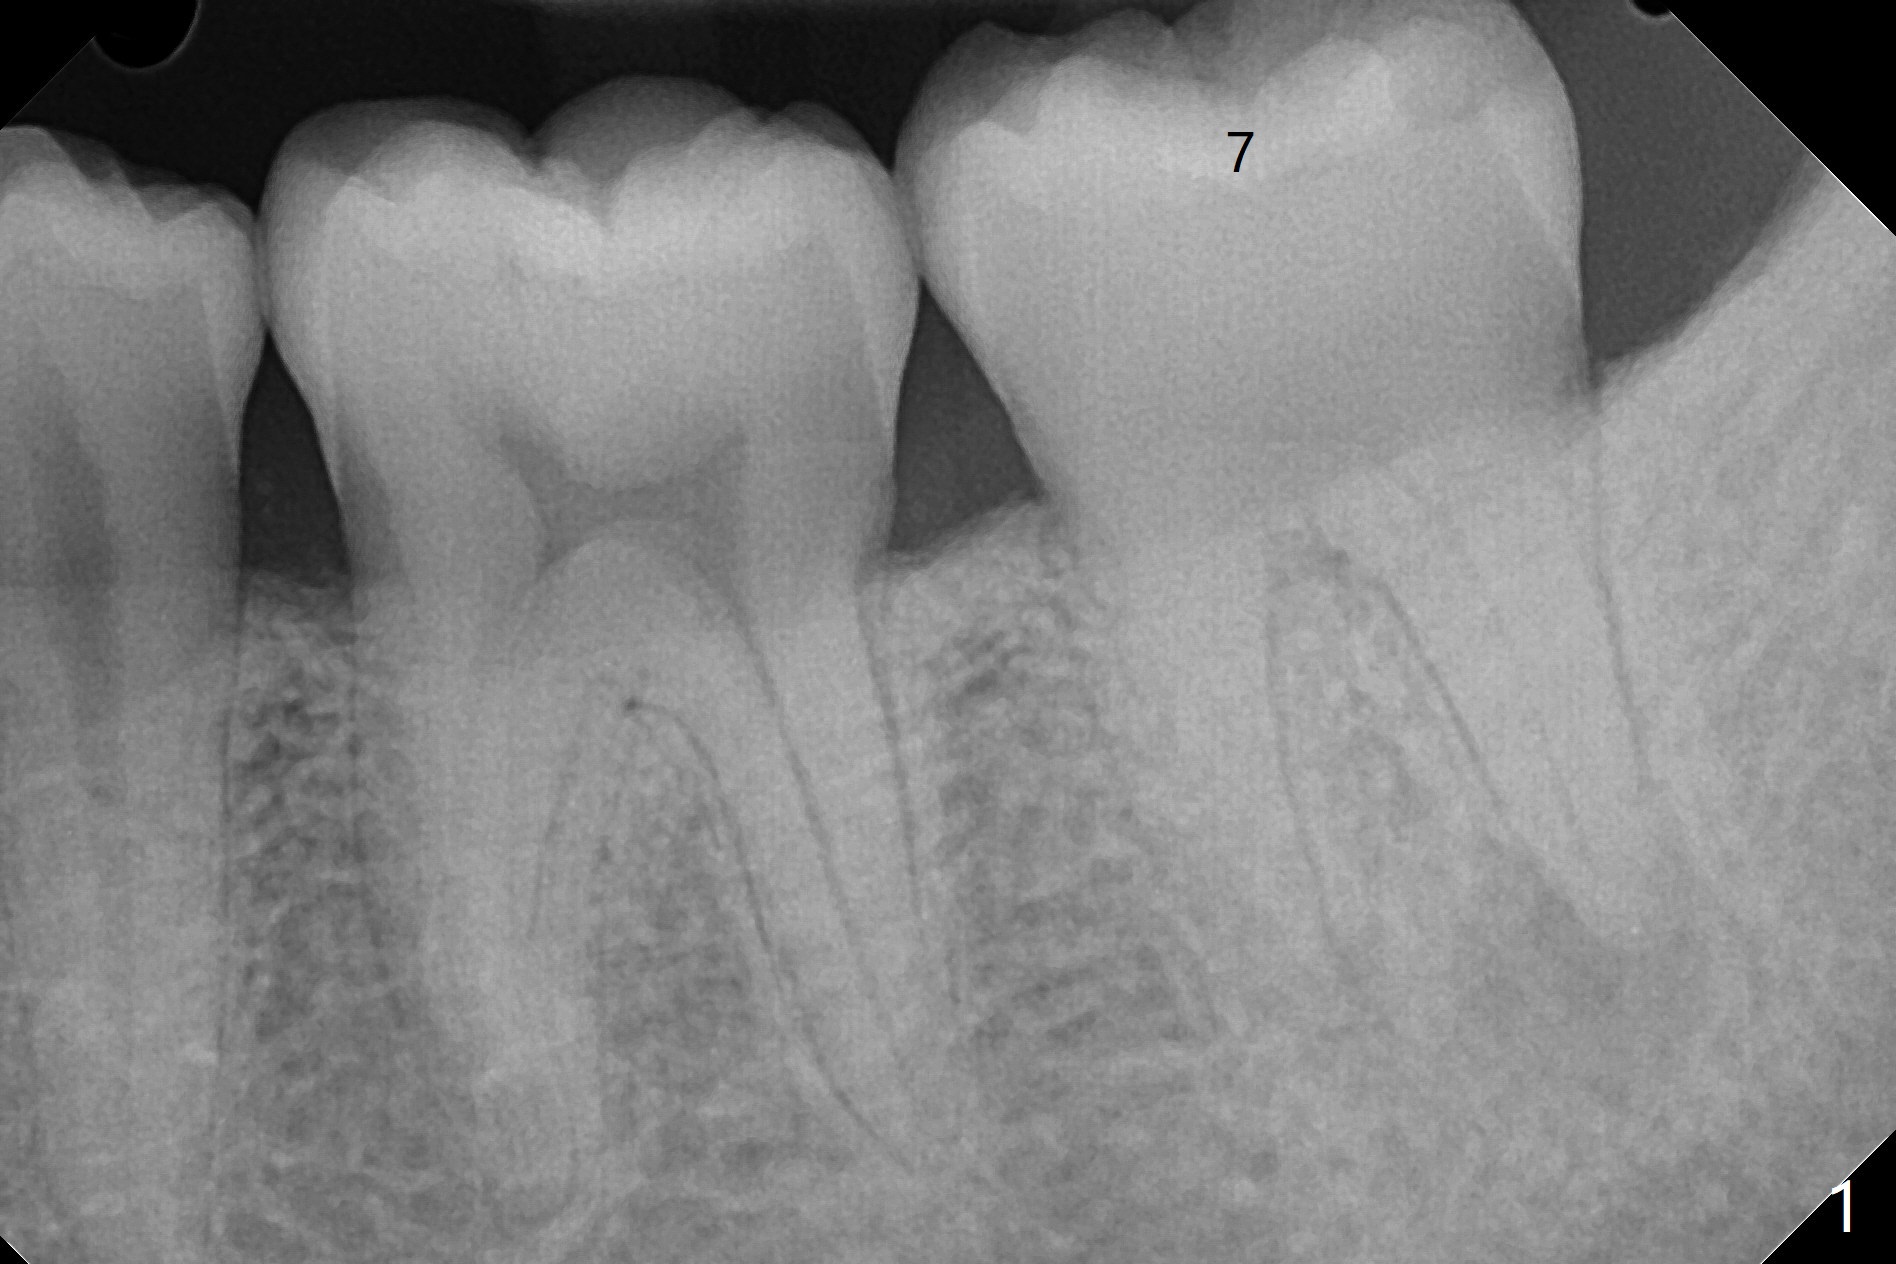

30岁男小的时候双侧下颌第二磨牙埋伏,拔除智齿后,前者经过矫正才萌出。近几年两个第二磨牙都出现疼痛,牙髓病专家认为左侧预后不佳(图一),需要拔除种植(图二)。注意去除根尖肉芽组织。左下7治疗完成后病人要求右下7拔除植牙(图三,四)。